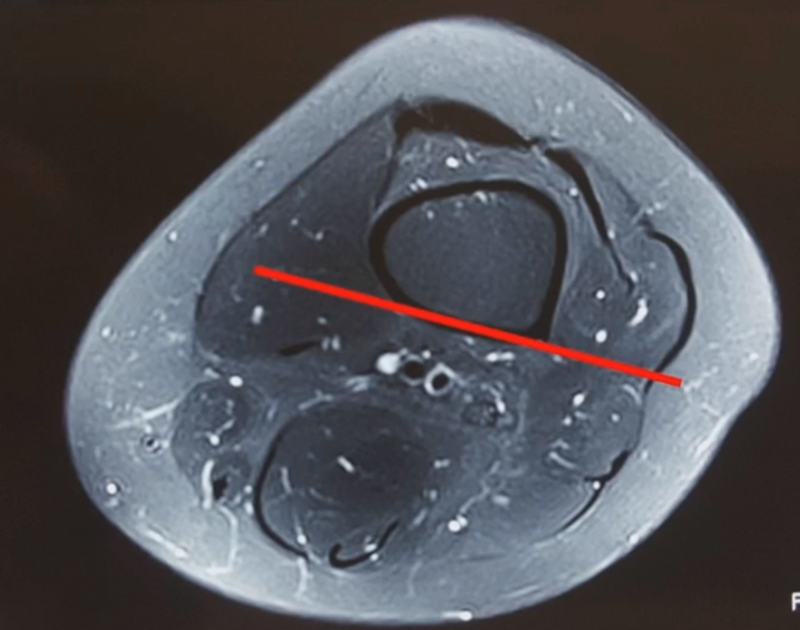

1、入路

股内侧肌间隙,在股骨远端做纵行切口,通过股内侧肌后侧间室,将股内侧肌向前方拉开,显现股骨近端远侧骨面。